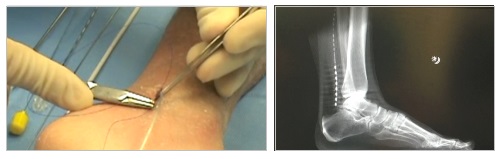

- Χειρουργική απελευθέρωση του νεύρου